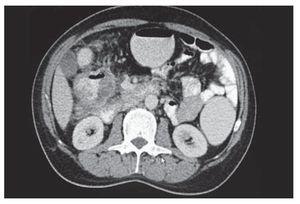

Se trata de un hombre de 54 años con antecedente de cáncer de colon en tres tíos maternos, cuatro primos y tres sobrinos, así como cáncer de páncreas en dos sobrinos. Todos ellos fueron diagnosticados entre los 35 y 55 años. El paciente tenía historia de hemorragia del tubo digestivo bajo de un mes de evolución. También presentaba dolor abdominal en mesogastrio tipo cólico e intermitente. A la exploración física se encontró hiperbaralgesia en el mesogastrio y dentro de sus exámenes de laboratorio presentó anemia ferropénica. Se le realizó una esófagogastroduodenoscopia y una colonoscopia que detectaron gastropatía no erosiva y una lesión de aspecto neoplásico en ángulo hepático del colon con patrón infiltrante y una zona de estrechez. Las biopsias de la mucosa obtenida de ese sitio demostraron un adenocarcinoma. Mediante una tomografía se observó un tumor colónico ulcerado en el ángulo hepático de 10 cm en su eje mayor con invasión al duodeno (Figura 1). El paciente recibió nutrición parenteral preoperatoria por una semana. El valor del antígeno carcinoembrionario fue de 17 mcg/L. En la laparotomía exploradora se demostró invasión del tumor al duodeno y al páncreas (Figura 2). Se le realizó una pancreatoduodenectomía clásica y hemicolectomía derecha en bloque, con resección lateral de la vena mesentérica superior (Figura 3). El estudio histopatológico definitivo demostró un carcinoma poco diferenciado con aspecto medular de colon derecho que invadió duodeno, páncreas y estómago, pero con bordes y ganglios linfáticos negativos, de entre 31 que se analizaron, por lo que se calificó como T4N0M0 (Figura 4). Se realizó estudio inmunohistoquímico de MSH-6 y MLH-1, en los que se demostró presencia de marca nuclear en la mucosa residual y en las células epiteliales neoplásicas, resultados sugerentes de estabilidad de las enzimas de reparación del ácido desoxirribonucleico (DNA) estudiadas. En el periodo posoperatorio, el paciente desarrolló una fístula pancreática y un cúmulo intraabdominal secundario; la fístula se trató con una punción guiada por tomografía, antibióticos y nutrición parenteral.

Figura 1. Tomografía que muestra una tumoración en el ángulo hepático del colon con probable invasión del duodeno.